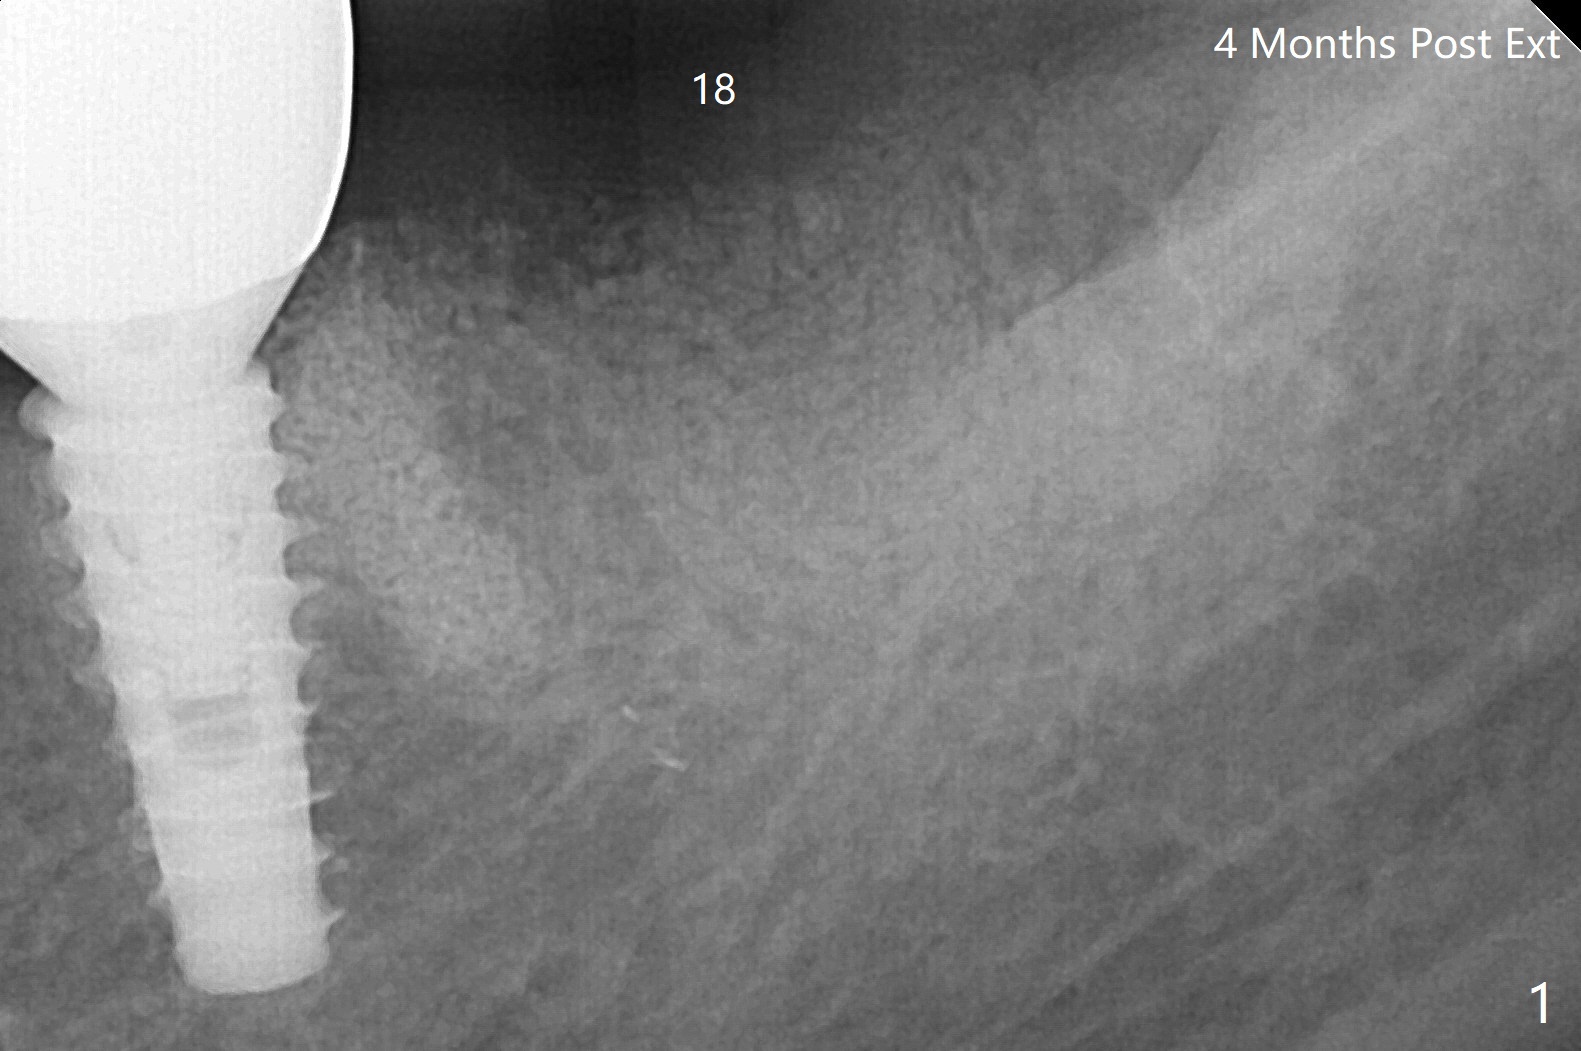

A 55-year-old woman is going to have implant placement at #18 using surgical guide 5 months post socket preservation (Fig.1). The bone density of initial osteotomy until 3.5x7.3 mm drill seems to be soft (Fig.1,2). Underprep is decided for the remaining osteotomy (Fig.3). The last drill is 3.5x10 for 4.5x10 mm implant (Fig.4). In fact initial insertion torque is >55 Ncm. The implant has to be backed up several times to get final torque ~ 35 Ncm. Retrospectively the bone density of the lower portion of the osteotomy is higher than that of the upper one (compare Fig.2,3). There is crestal bone (grafted one *) resorption 4 months postop (Fig.5).